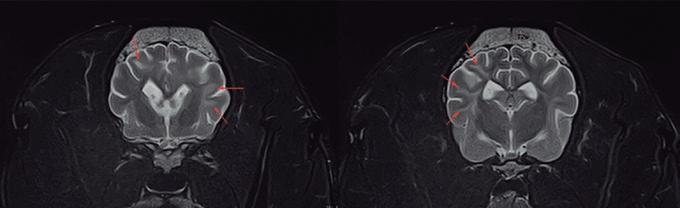

La radiología intervencionista es una especialidad que se encarga del diagnóstico y tratamiento de una gran cantidad de patologías de una forma mínimamente invasiva. Para realizar estos procedimientos es imprescindible disponer del equipamiento adecuado, tener nociones tanto de la instrumentalización como de las diferentes técnicas, y conocer con precisión la anatomía del paciente. Se trata de técnicas cada vez más implementadas en la clínica diaria ya que permiten solucionar diferentes patologías con una menor agresión a nivel tisular, una rápida recuperación, son procedimientos sin dolor, rápidos y seguros, suponen un menor coste respecto a otras cirugías invasivas, y constituyen una alternativa terapéutica a pacientes que no se pueden operar de forma convencional. Entre las más frecuentes destaca el cierre del conducto arterioso persistente, valvuloplastias en estenosis pulmonar, oclusión de shunts portosistémicos, implantación de marcapasos y colocación de stents

La radiología intervencionista, también conocida como radiología vascular e intervencionista, es una especialidad que se encarga del diagnóstico y tratamiento de una gran cantidad de enfermedades de una manera mínimamente invasiva. Se realiza mediante un abordaje guiado por distintas técnicas de imagen como, por ejemplo, la ecografía, la fluoroscopia o la tomografía computarizada, para alcanzar la zona a diagnosticar o tratar.